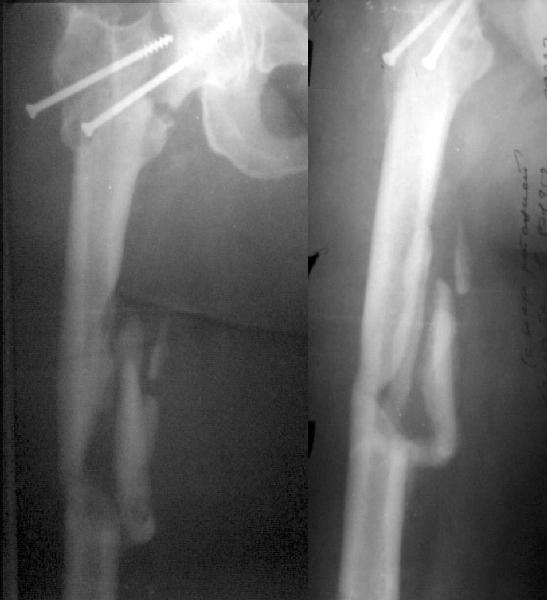

Примерно год назад женщина 44 лет оперирована по поводу перелома шейки и диафиза бедра через 2 нед. после автоаварии. Сделали закрытый остеосинтез бедра стержнем и попытались синтезировать шейку мимо гвоздя.

Пролучилось плохо (снимок N1, через 1 мес. после операции), отчасти благодаря тому, что окружность бедра в верхней трети у нее больше 80 см. Гвоздь на днях удален через старые разрезы. Шейка, понятное дело, не срослась, а диафиз - только на ограниченном участке (снимок N2).Встает вопрос - что делать дальше? Думаем про вальгизирующую остеотомию с фиксацией клинковой пластинкой. Может быть, с ретроградным штифтованием бедра (хотя места между переломом и нижним концом пластинки маловато). Эндопротез с длинной ножкой не доступен. Ожирение - прежнее. Заранее спасибо.

This is a good example of sub optimal placement of the neck screws. Young patients with neck/shaft combo fxs have a high Pauwells' angle. This is counteracted by open reduction and internal fixation in order to reduce caudal portion of fem neck. The screws are angled differently by placing them perpendicular to the fem neck fx line (typical AO technique) or horizontal to the floor. The screws here are similar to elderly fem neck fx types. Therefore, no biomechanical advantage exists and the nonunion is produced.

You need to perform a valgus osteotomy with 130 osteotomy plate. This will improve the relative Pauwells' angle and improve the union rate. Problem is the probable nonunion or partial union to the shaft. The osteotomy plate is

only made with 6 holes which will not allow for bypassing the shaft problem.

You will probably require an open plating and bone grafting. Try to angle your distal ost and prox shaft screws so that they overlap and theoretically decrease the stress riser created with the double plates.

The biggest problem here is the femoral neck nonunion in a 44 yo obese (?weight) patient. No femoral head AVN apparent on plain xray but a significant fracture gap with a verticle fracture line on AP. If you can get that to heal you will be doing her a great service. The femoral shaft is still secondary.

Сделали подвертельную вальгизирующую остеотомию (чуть низковато плучилось), синтезировали клинковой пластинкой. После компрессии и

латерализации винтом ниже остеотомии, нижний винт в пластинке заменен на 3 монокортикальных. Бедро ретроградно рассверлили и заштифтовали UFN 12 мм, верхний запирающий винт ввели через пластинку. Псевдартроз сдавился хорошо. Снимок в приложении. Буду рад услышать комментарии.

The valgus osteotomy has improved the position of the femoral neck fracture

The blade plate is in the anterior and proximal aspect of the femoral head

What activity level is planned? Keep a close eye on the femoral head and neck. They will determine outcome, primarily.